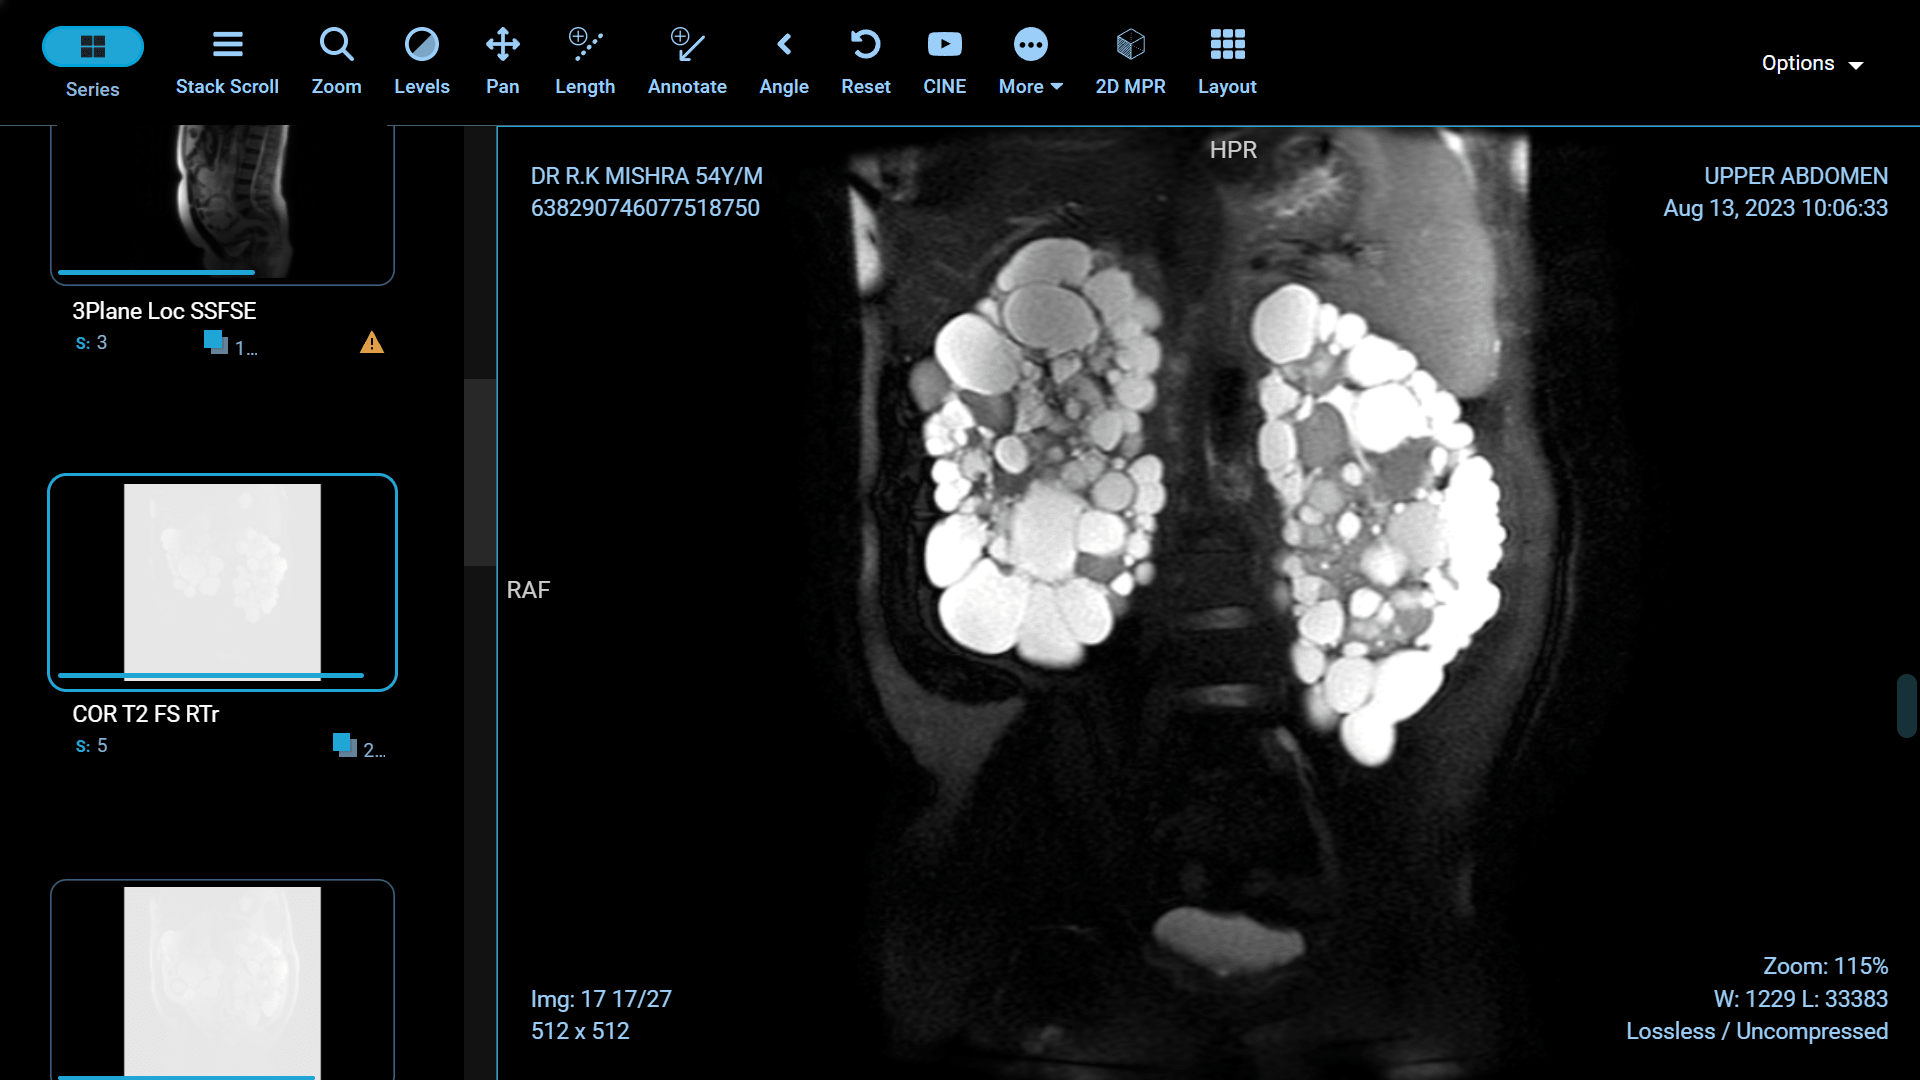

Polycystic Kidney Disease (PKD) is a genetic disorder characterized by the formation of fluid-filled cysts in the kidneys, which can lead to renal failure if left untreated. Fortunately, recent advancements in medical science have paved the way for more effective treatments and improved the quality of life for those affected by this condition. In this article, we will explore some of the groundbreaking innovations in PKD treatment.

Foam sclerotherapy is a medical procedure that involves injecting a specialized foam directly into kidney cysts. The foam is made by mixing a liquid sclerosing agent, typically a solution of alcohol or polidocanol, with air or gas to create a stable, persistent foam. This foam is then injected into the cyst through a thin needle under ultrasound or CT guidance.

The success of foam sclerotherapy lies in its ability to cause intentional injury to the cyst lining, promoting inflammation and scarring. This process leads to the collapse and sealing of the cyst, preventing further fluid accumulation and reducing the cyst's size.

Preservation of Healthy Kidney Tissue: Unlike some other treatments, foam sclerotherapy specifically targets the cyst, leaving the surrounding healthy kidney tissue intact. This is particularly important for individuals with only one functioning kidney.

Potential for Multiple Cysts: Foam sclerotherapy can be used to treat multiple cysts in one or both kidneys during a single procedure, reducing the need for multiple interventions.